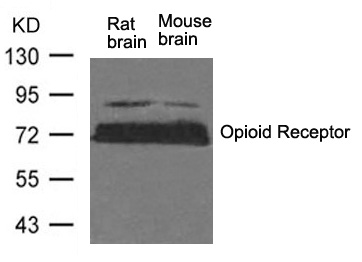

分类: 科研抗体货号: P41496别名: MOR; MUOR1; Mu-type opioid receptor; OPRM; OPRM1应用: WB反应种属: Mouse,Rat